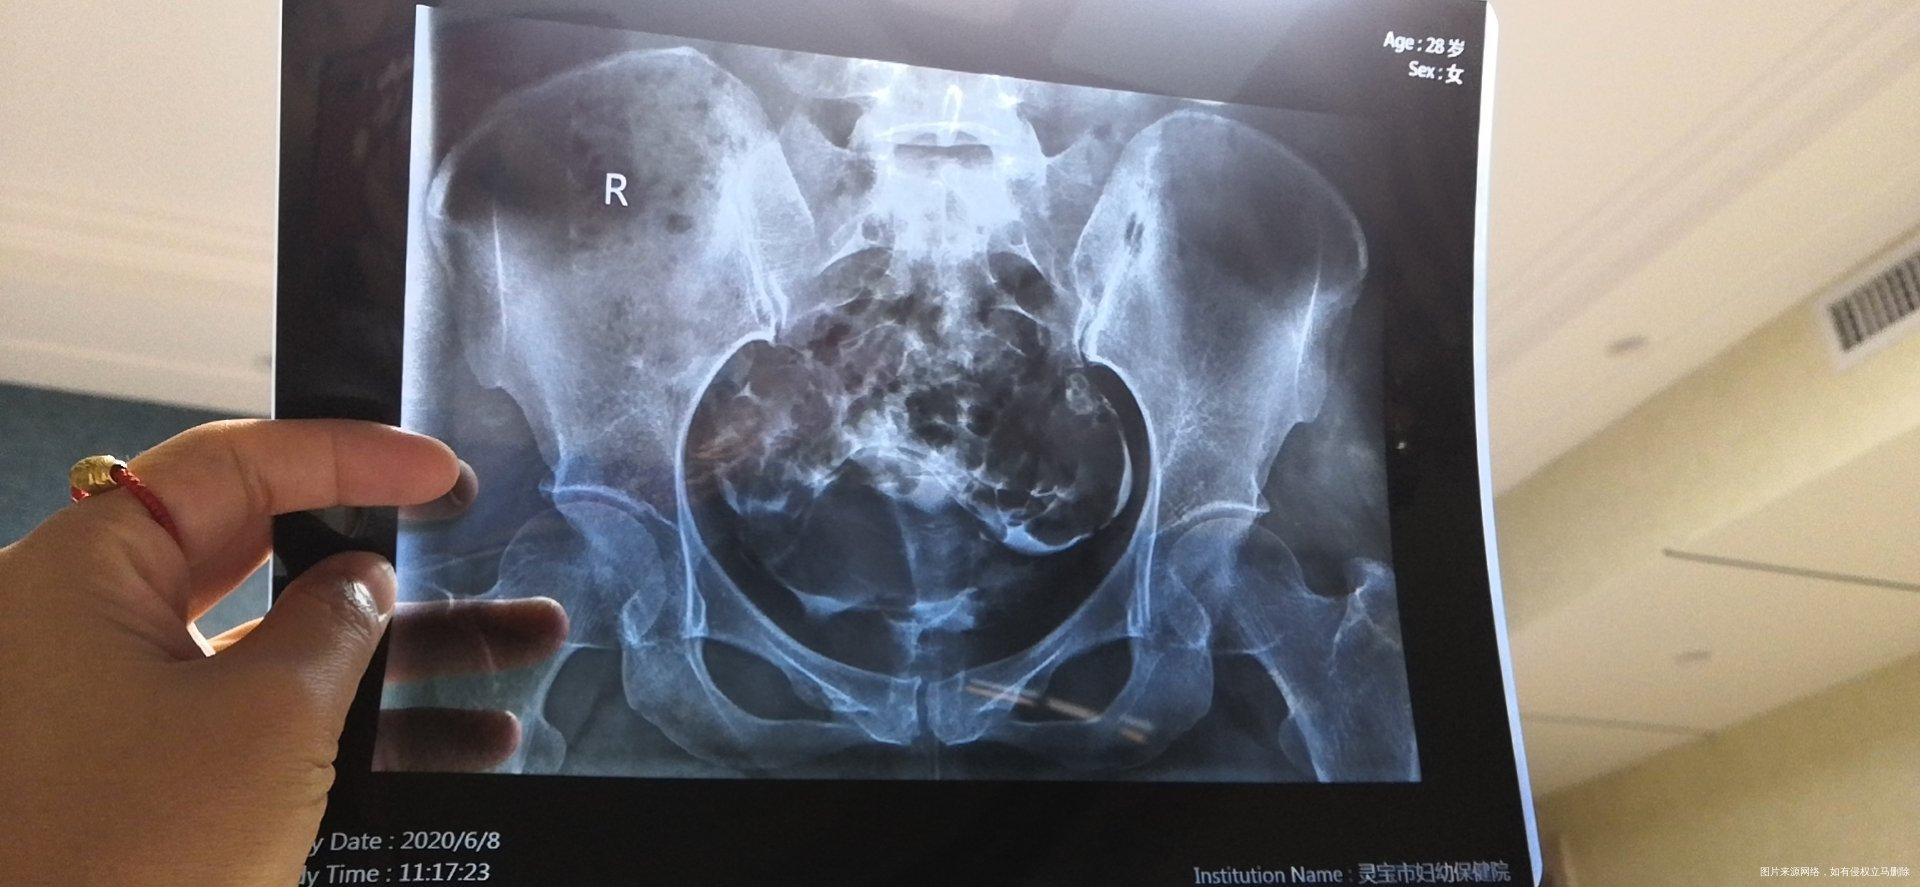

可以帮忙看一下输卵管片子吗?4个图的是第一次造影,去年九月做的,剩下两张图是今年五月份做的,现在一直在吃中药调理!

您好,今年拍的片子比去年好一点,但是从片子上看今年的双侧伞瑞仍然粘连